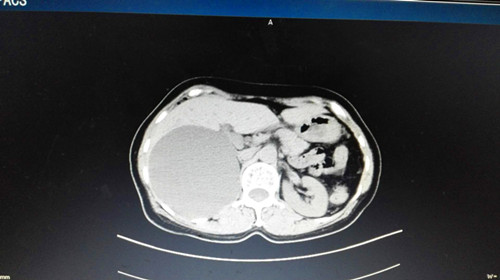

胃镜:非萎缩胃炎.上腹部CT平扫+增强:右肝内见一巨大低密度影,大小约9.5cmx10.1cm,边界清晰,增强后未见明显异常,右肾受压向下移位,右肝后叶下段亦见一小圆形低密度影,直径约0.4cm,增强未见明显强化。